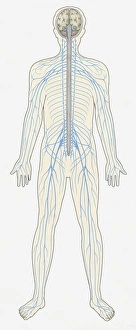

The central nervous system, the intricate network that governs our every thought and movement, is a marvel of complexity. From the delicate cerebellum tissue to the detailed light micrograph capturing its essence, we are reminded of its importance in maintaining balance and coordination. Anatomy comes alive as we explore the human brain from an inferior view. The intricacy of brain fibers is revealed through DTI MRI scans like C017/7099 and C017/7035, showcasing their vital role in transmitting information throughout this extraordinary organ. Artistic renderings bring us closer to understanding the medulla oblongata's significance within the brain. Its portrayal in various artworks allows us to appreciate how it controls essential functions such as breathing and heart rate. As we delve deeper into studying the central nervous system, models of the human brain provide invaluable insights into its structure and organization. Lateral views reveal countless regions responsible for cognition, emotion regulation, sensory perception, and motor control. Microscope slides offer glimpses into nerve cells' intricate architecture—a testament to their ability to transmit electrical signals at lightning speed. Meanwhile, glial stem cell cultures captured under a light microscope remind us of their crucial role in supporting neuronal function. Finally, artistic representations unveil the limbic system's enigmatic nature—an interconnected web responsible for emotions and memory formation. These captivating artworks allow us to visualize this complex network within our brains. Exploring these hints provides a glimpse into the awe-inspiring world of our central nervous system—the very foundation upon which our thoughts, actions, memories reside—reminding us just how remarkable our brains truly are.